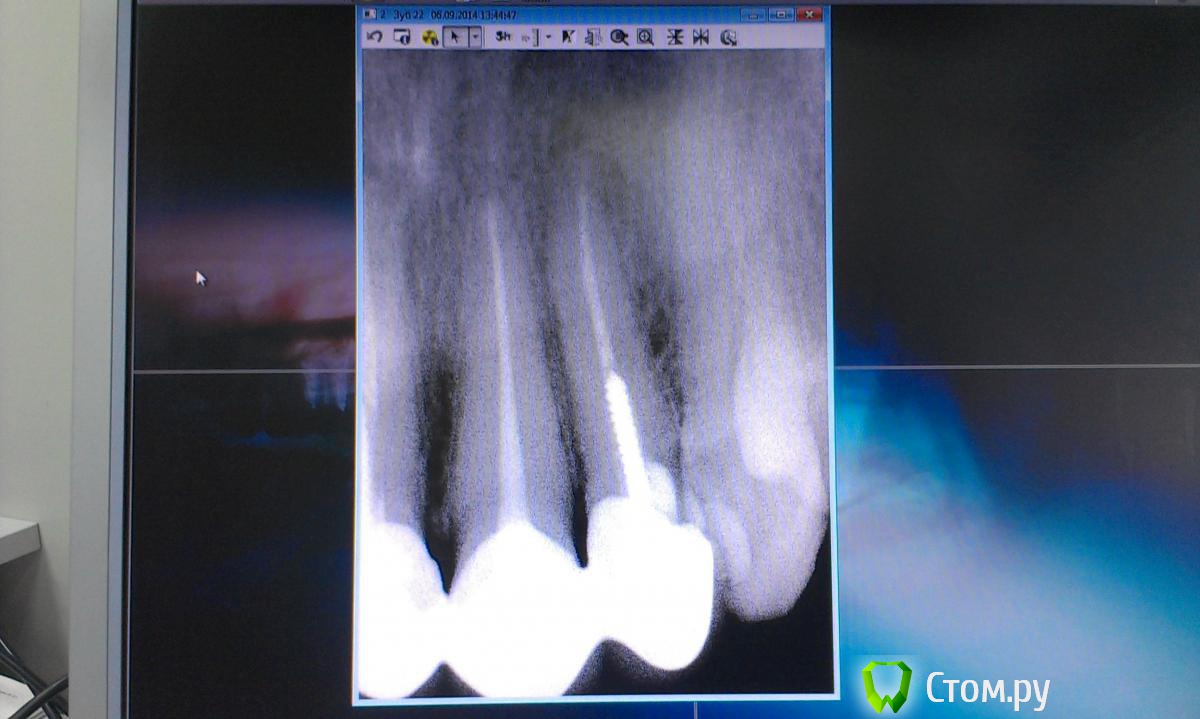

Ольга97-99 Опубликовано 6 сентября, 2014 Поделиться Опубликовано 6 сентября, 2014 Добрый день, уважаемые стоматологи. Прошу помощи... Ситуация с зубами плачевная... Не буду долго расписывать о том, как с 10 лет я не вылезаю из кресла стоматолога. Леченые зубки в небольном городе Н. Постоянно выпадающие пломбы, приводящие к повторному лечению. Депульпированны практически все. Периодичность посещения стоматолога - 3 мес., + манипуляции парадонтолога. Но к 26 годам имеем нижепредставленное.. С задними зубами все более или менее ясно - еще несколько на удаление, затем имплантация. С передними верхними... МК коронкам 7лет. Не беспокоят, боли, дискомфорта нет. Но эстетика оставляет желать лучшего. Еще, как говориться, не везет так не везет - улыбка десневая. И поднявшаяся синюшная десна во всю сияет. Было решено - настало время перемен. Мой обход ортопедов в нашем славном городе начался с мыслью вдохновляющей "заменить мк на дц". Более натуральный вид, к тому же рецессия десны должна была остановиться, так Интернет и доктора говорили )). Что имеем сейчас, мнения двух (на мой взгляд самых адекватных спецов) ортопедов: Первый: снимаем коронки, смотрим состояние корней. Если все нормально, штифты не трогаем, меняем пломбы и делаем дц. Но 80-90% вероятность, что корни испортились, либо будут повреждены (при снятии коронки выйдет штифт, разрушив корень). Тогда удаление, затем имплантация. Не буду портить мнение о себе и писать, что я испытывала после такого вердикта.... Второй: (его, кстати, посоветовал 1й) глянул (бегло) на мой снимки, говорит: снимаем коронки, вынимаем штифт, лечим каналы, делаем вкладки из дц, делаем коронки из дц. На мой вопрос "а если корень поврежден? или еще что-то не так пойдет" был ответ "зачем тебе это все знать, я доктор и я говорю тебе - будут коронки нормальные". Думаю, не стоит уточнять, что гарантий по сроку службы новых коронок я не услышала. Ну верней, прозвучала классика про кирпич на голову. Понятно, какой вариант мне запал в душу, и чего я бы хотела.. Но я могу хотеть одного, а реальность может быть совсем другой.. Не имею право на неоправданный риск, это же передние зубы... Пожалуйста, посмотрите снимки. Можно услышать Ваше мнение насчет возможности замены протезов передних верхних зубов. Заранее спасибо!!! Ссылка на комментарий

Korel Опубликовано 8 сентября, 2014 Поделиться Опубликовано 8 сентября, 2014 Вопрос о состоянии корней остается открытым до момента снятия коронок, я правильно понимаю? Нет, не правильно. Ваши корни видны на R-снимке. Открытым остаётся вопрос о состоянии культей скрытых коронками. 1 Ссылка на комментарий